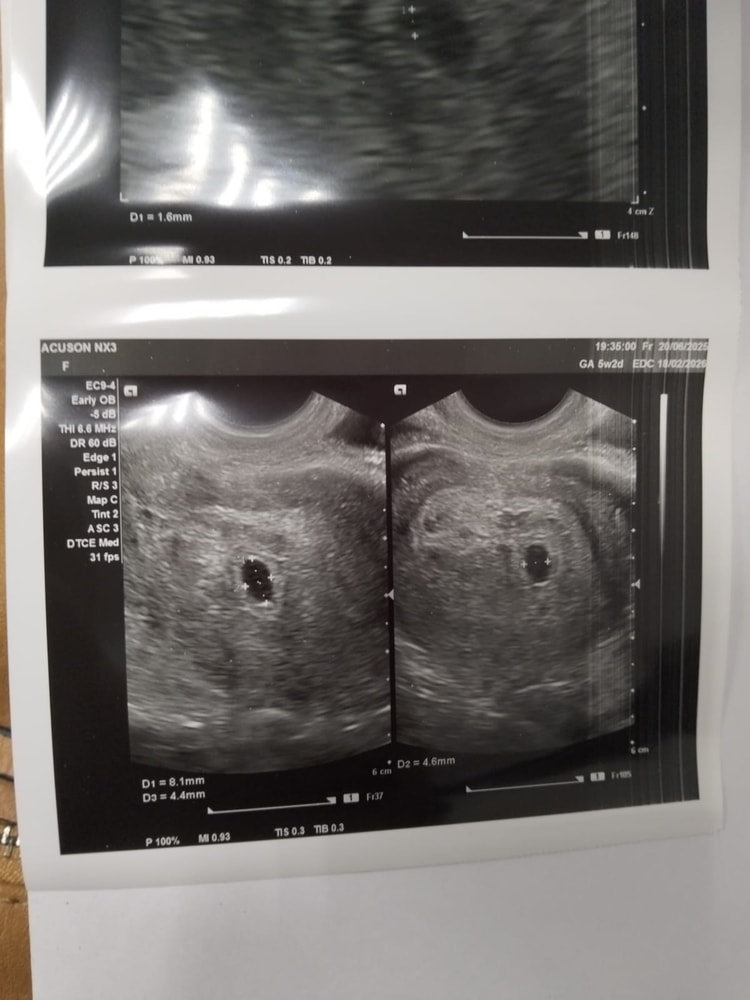

Запись о симптомах. Было УЗИ 20июня, где нашли ПЯ в матке, пока без эмбриона, и я успокоилась. Срок по ПЯ поставили 5н2д, срок с месячных - сегодня пошла седьмая неделя. Не понимаю на каком я в итоге сроке 😆

Сходила на УЗИ только что. ПЯ 5,7 и желточный мешочек 1,6мм - срок 5,2 недель по месячным.

Вот оно. Моё. Боже!!!

Но эмбриона пока не увидели - рано.